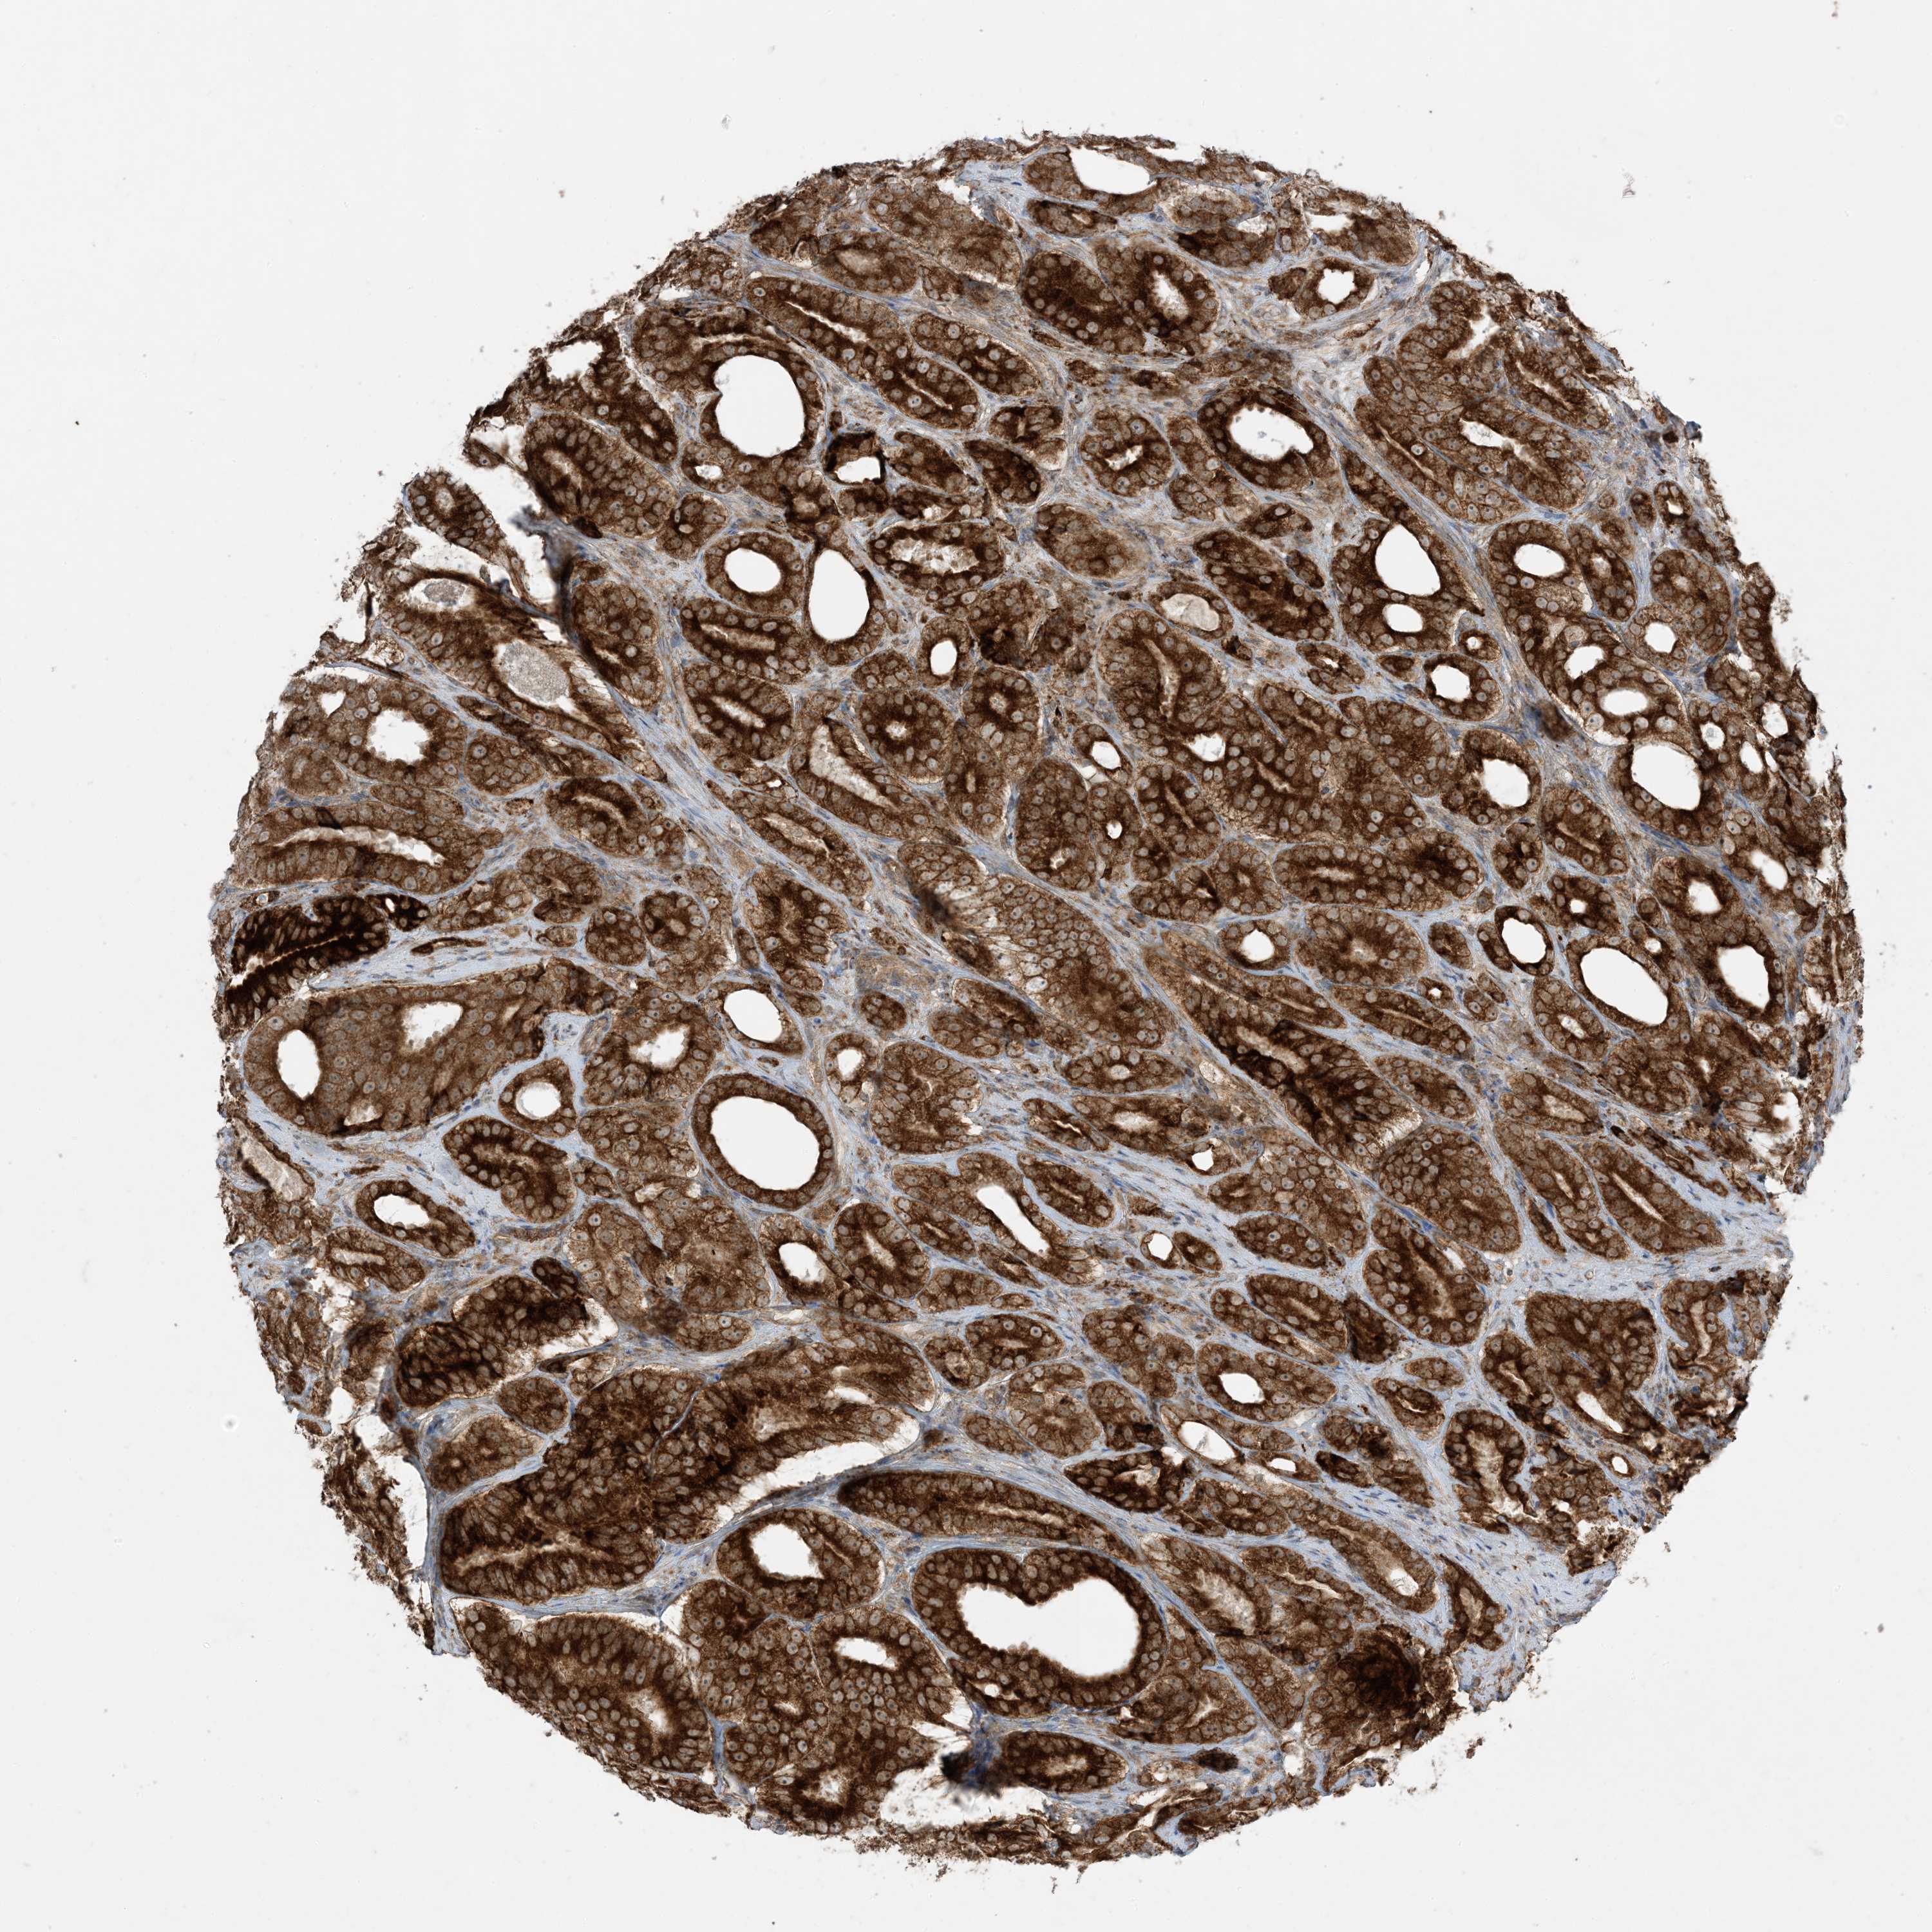

PROSTATE CANCER - Protein expressioni

A mouse-over function shows sample information and annotation data. Click on an image to view it in a full screen mode. Samples can be filtered based on level of antibody staining by selecting one or several of the following categories: high, medium, low and not detected. The assay and annotation is described here.

Note that samples used for immunohistochemistry by the Human Protein Atlas do not correspond to samples in the TCGA dataset.

Antibody stainingi

Antibody staining in the annotated cell types in the current human tissue is reported as not detected, low, medium, or high, based on conventional immunohistochemistry profiling in selected tissues. This score is based on the combination of the staining intensity and fraction of stained cells.

Each image is clickable and will lead to virtual microscopy that enables deeper exploration of all samples and also displays staining intensity scores, fraction scores and subcellular localization as well as patient and tissue information for each sample.

Antibody HPA001536

Antibody CAB035996

Staining

High

Medium

Low

Not detected

Intensity

Strong

Moderate

Weak

Negative

Quantity

>75%

75%-25%

<25%

None

Location

Nuclear

Cytoplasmic/membranous

Cytoplasmic/membranous,nuclear

Adenocarcinoma, Medium grade

Adenocarcinoma, High grade

Adenocarcinoma, Low grade